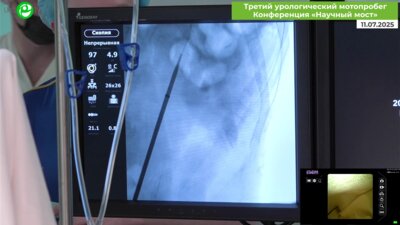

Мочекаменная болезнь